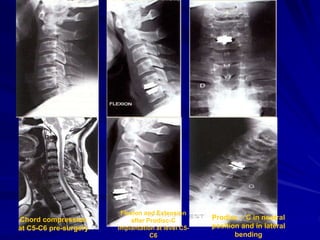

Chord compression at C4-C5 left side

Lateral view after

Prodisc-C implantation

ΑΡ view after

Prodisc-C implantatio

MRI pre-surgery.

DDD multilevels -

Chord

compression at C4-

C5

Chord compression

at C5-C6 pre-surgery

Flexion and Extension

after Prodisc-C

implantation at level C5-

C6

Prodisc – C in neutral

position and in lateral

bending